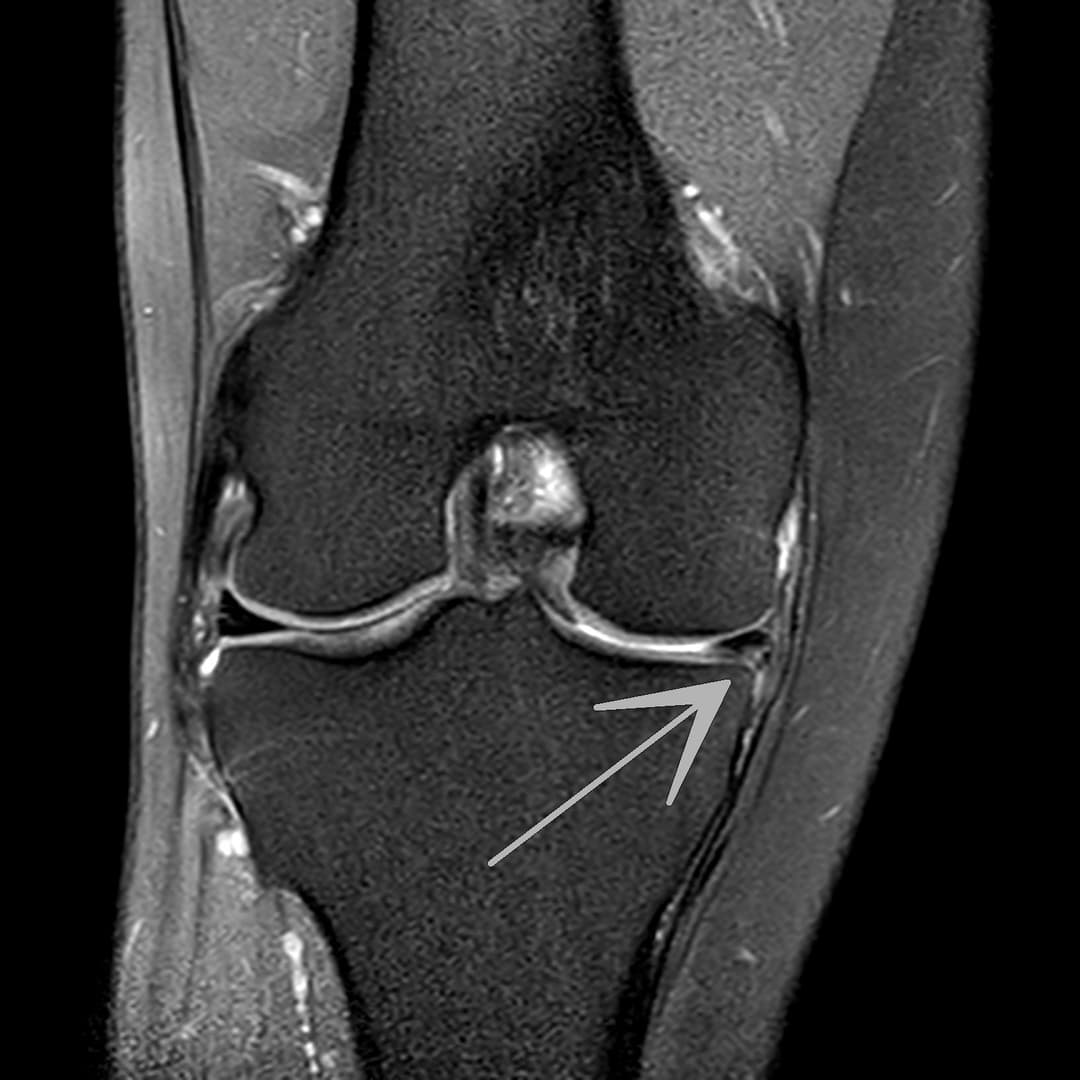

Fissure de grade 3 du segment moyen du ménisque médial.

Languette méniscale rattachée à la corne antérieure du ménisque médial avec aspect flottant sur le versant antérieur de l'échancrure.